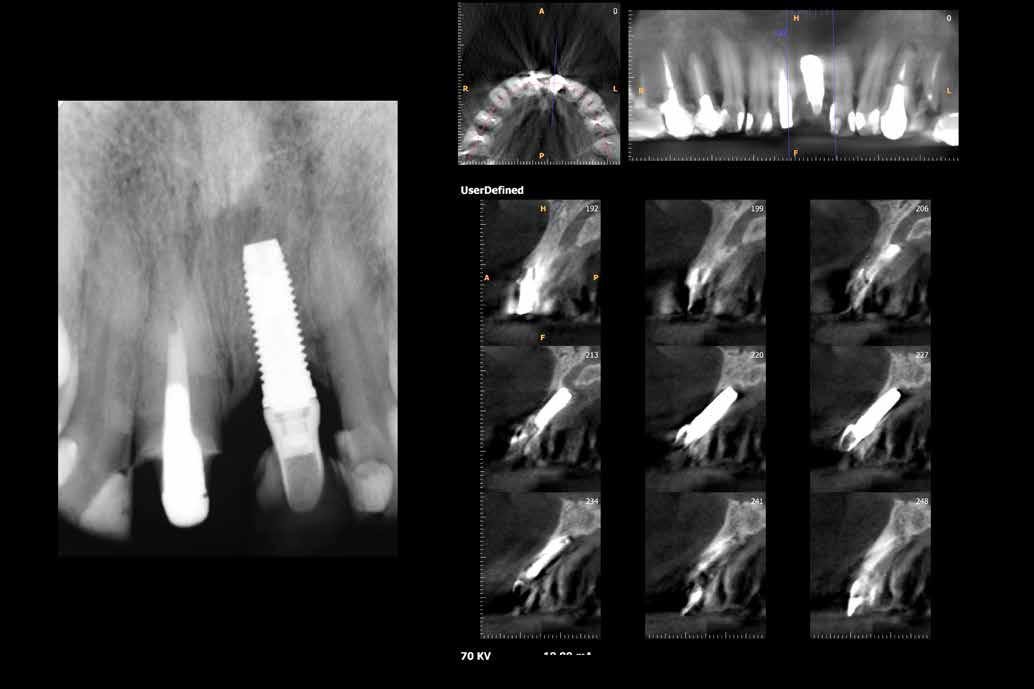

Egy 35 éves kaukázusi férfi páciens az 1.4-es fog (felső első premoláris) törése miatt kereste fel rendelőnket, a törés ferde volt. A sérült fogak helyreállítása során az egyik legfontosabb lépés a megmaradt fogazat biomechanikai értékelése . Egy hiba ebben a fázisban káros a hosszú távú eredményre . A legtöbb repedést például a fogüregek helyreállító fogászathoz való helytelen előkészítése okozza. Ugyanígy a fennmaradó szerkezet helytelen értékelése idővel mechanikai okokból bekövetkező meghibásodáshoz vezethet.

2. ábra: Az okkluzális nézet a fogszerkezet mennyiségét mutatja, a röntgenfelvételen az 1.5. fogon II. osztályú szuvasodás is látható. Még ha lehetséges is ezeket az eseteket koronahosszabbítással kezelni, a végeredmény átlagosan nem kielégítő. A ferrule gyógyulása korlátozott, és olyan parodontális szövődményekkel is találkozunk, mint a fekete háromszögek, a szomszédos fogak gyökérkitettsége. A fogszabályozó extrúzió sokkal előnyösebb.

4. ábra: A fogszerkezet helyreállítása és a fogrestaurációs komplexum ellenálló képességének javítása érdekében ortodontikus extrúziót végeztek a szomszédos fogakra ragasztott drót és egy egyszerű rugalmas ligatúra segítségével.